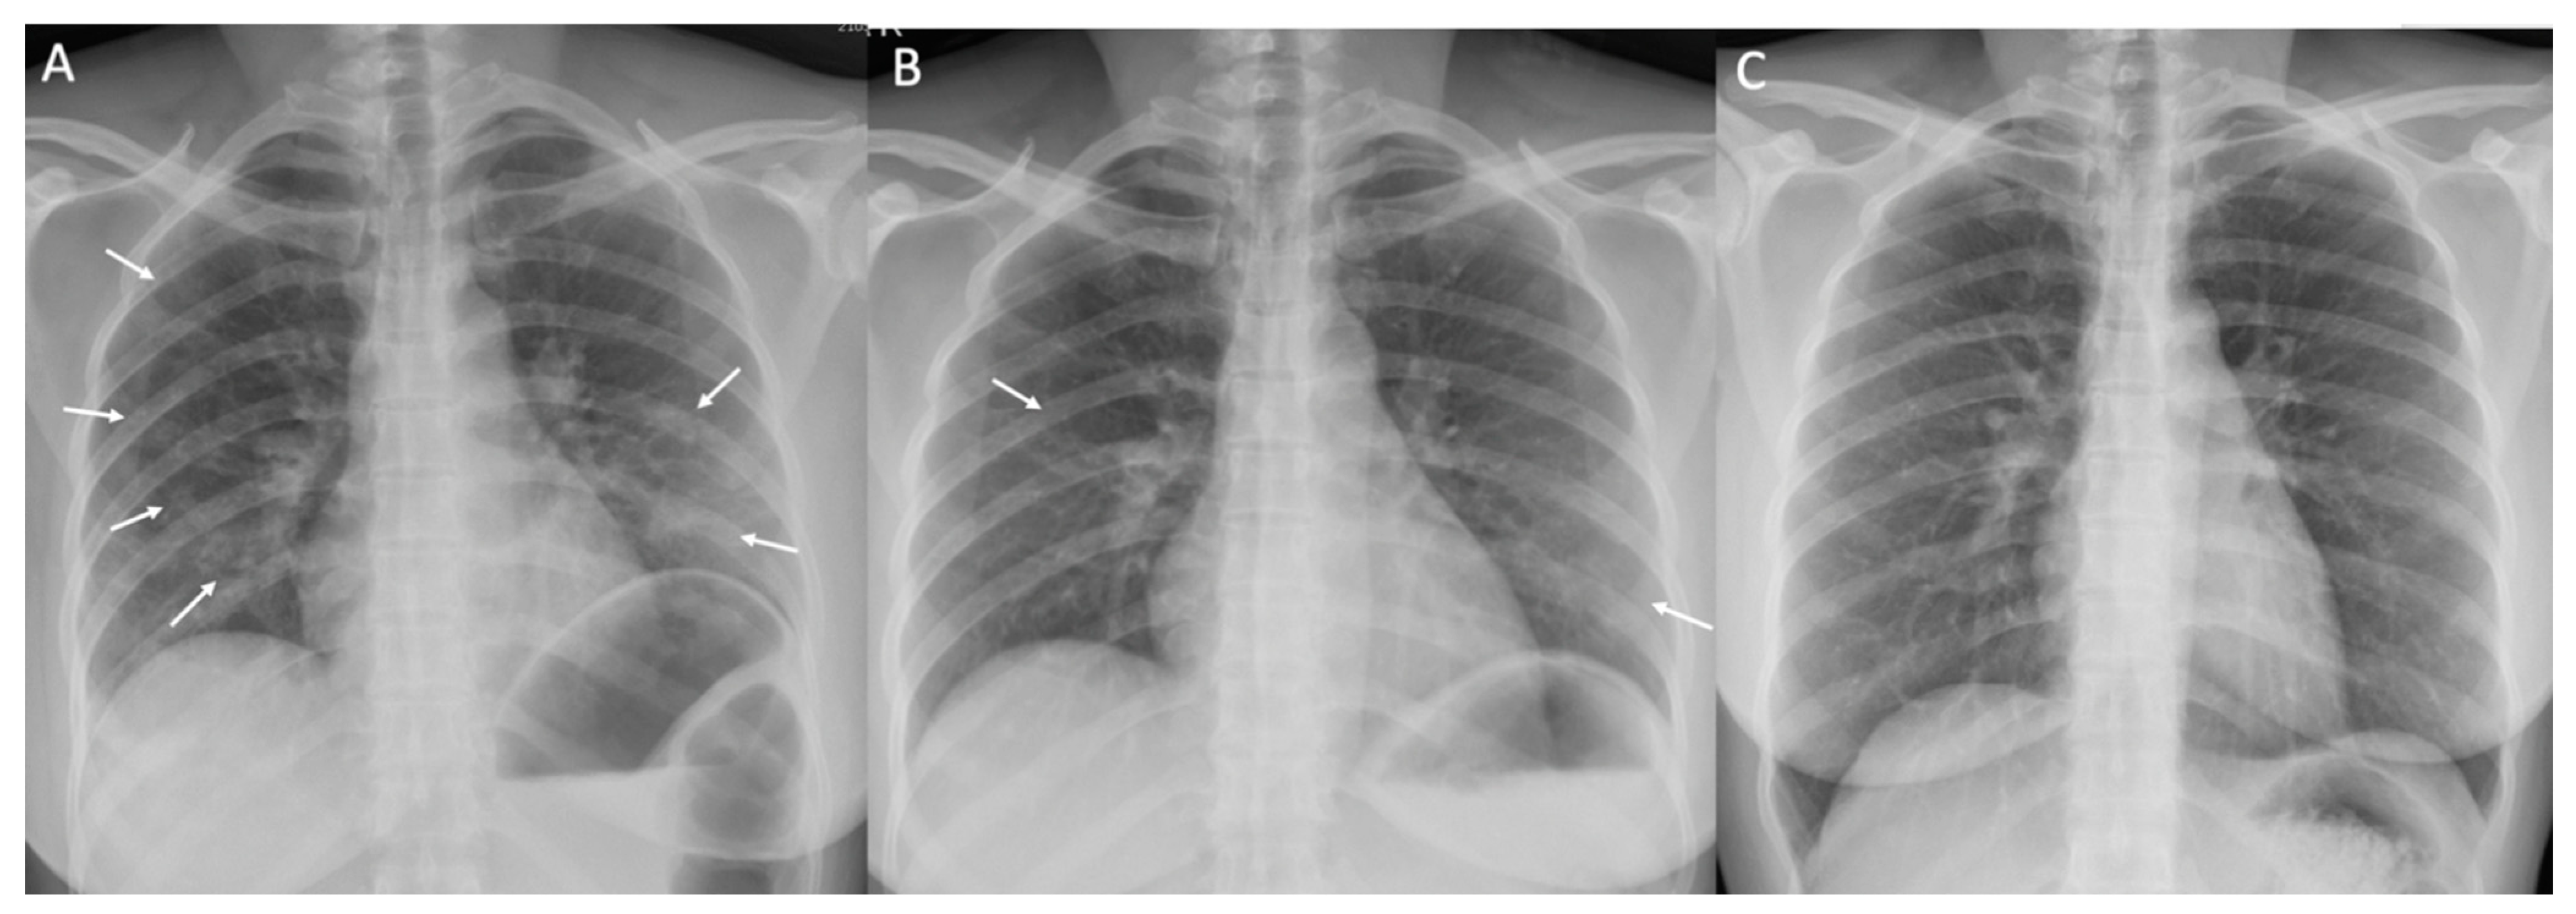

| Normal chest X-ray on DOI 1–3, n (%) | 211/290 (72.7) | 47/57 (82.5) | 163/231 (70.6) | 1/2 (50) | 0.136 |